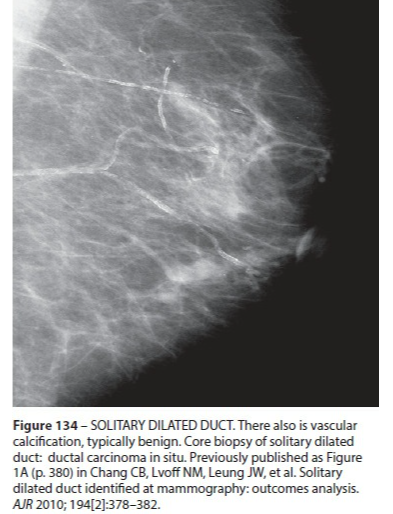

Ectasie Canlaire Solitaire

- Rare

Ectasie Canlaire Solitaire